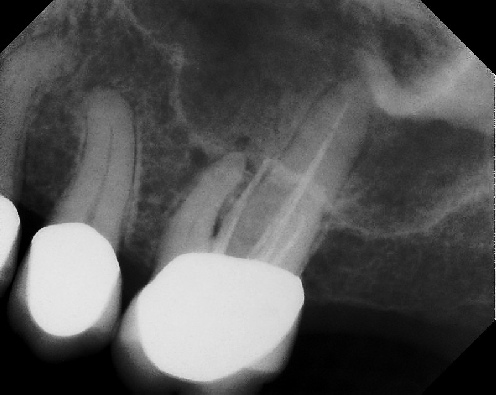

COMPLICATED ANATOMY LARGE LESIONS CALCIFIED CANALS PERFORATION / RESORPTION SEPARATED INSTRUMENTS SURGICAL CASES RETREATMENT / pOST REMOVAL OPEN APICES ACCESS THRU CROWNS Root Canal Case Portfolio